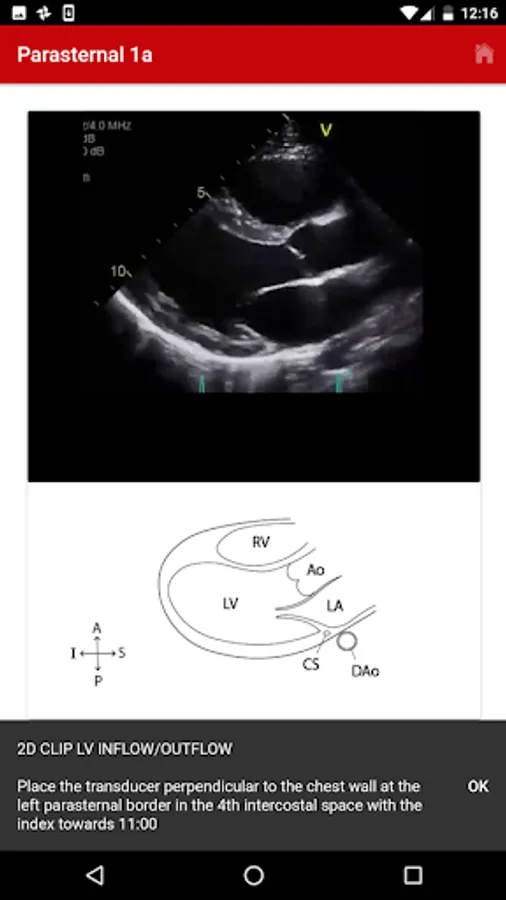

2. Parasternal

The exact images and the order in which the images and views are obtained varies by institution. Each protocol (subcostal, parasternal, apical or suprasternal) can be followed in order by clicking on the next tab at the bottom of the page or you can click on an individual numbered view within the protocol list to be taken directly to that view. The name of the view and instructions will pop-up automatically at the bottom of the page. The instructions and additional notes can also be found in the “NOTE” button at the bottom of the page.